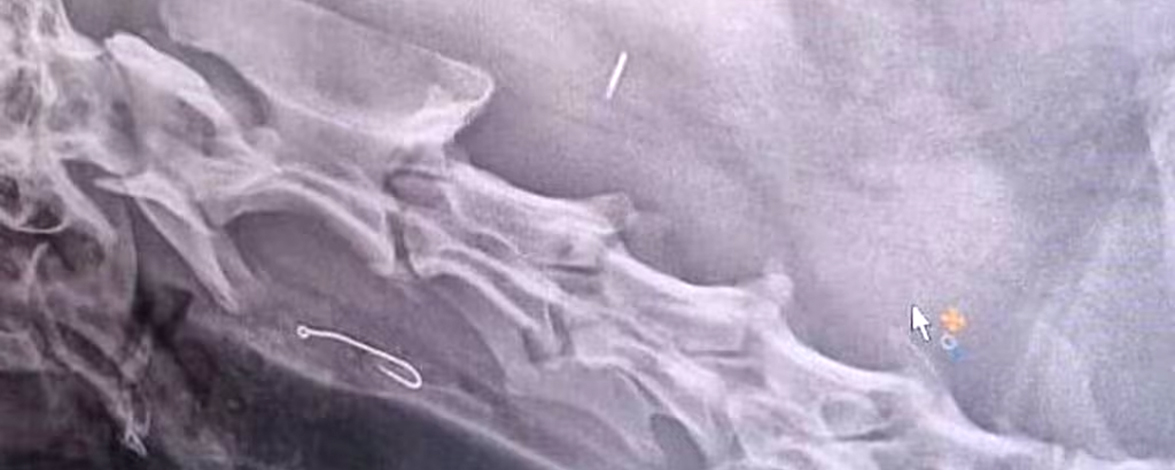

"Het was een hele lange lijn, met lood en haken en stukjes vis eraan", vertelt Valster aan RTL Nieuws. "Ik ben nog nooit zoiets tegengekomen op het strand." De restjes vis aan het dunne lijntje verdwijnen binnen een paar seconden, met lijn en al, in de bek van Django. Valster belt de dierenarts en kan meteen terecht in Goes. Op de röntgenfoto blijkt de haak vast te zitten in zijn slokdarm. Twee uur lang probeert de dierenarts het eruit te krijgen met een tang, maar zonder resultaat.